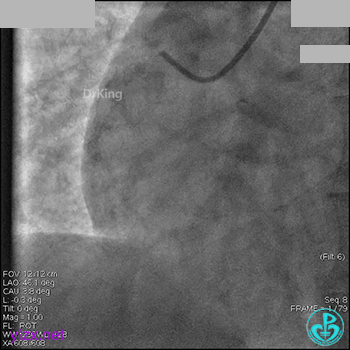

冠脉造影

入院次日冠脉造影显示粗大左主干末端中度狭窄,前降支开口严重狭窄,回旋支与前降支角度大,弥漫性长病变,严重狭窄,粗大右冠脉近中段弥漫性中重度狭窄。由于病变复杂,造影结束后先下台,择期再行介入治疗。